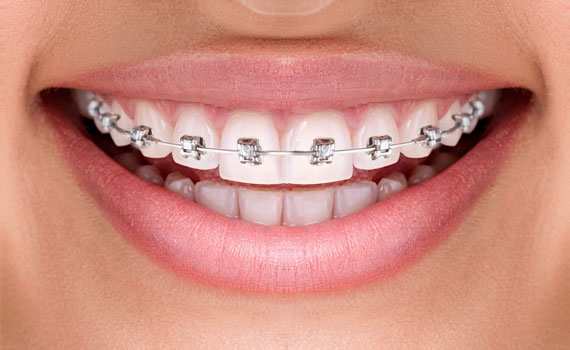

Ortodonti

Diş çapraşıklıkları çocukluk döneminde süt dişlerin yerini asıl dişlerin alması ile başlayan bir süreçtir.